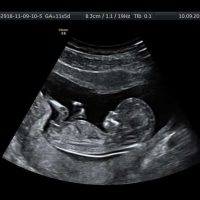

Sonography

Ultrasound scans used to evaluate uterus, ovaries, and follicle development, supporting diagnosis and monitoring throughout infertility treatment in Wakad.